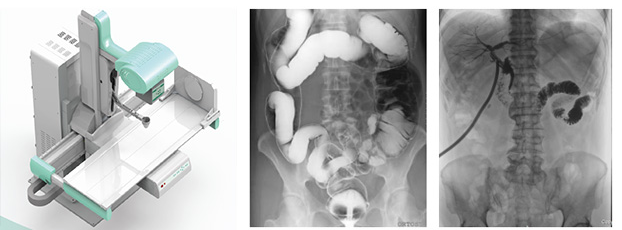

動態DR

動態DR是一款多功能DR,能夠數字拍片、數字透視、數字造影。

動態DR是使用多功能動態數字化探測器成像的直接數字化X射線攝影系統。

動態DR具有大幅面(17inch×17inch)高清拍片、大幅面(17inch×17inch)透視、視頻實時保存回放、可視化造影、毫秒級點片等基礎功能,以及斷層融合、數字減影等延展性功能。

普愛醫療作為全球較好的數字影像設備供應商,專注于DR系列產品的技術創新,在全國范圍內率先推出動態DR。以其“一機多用”集常規拍片、胃腸、透視、造影于一體的多功能作用深受放射科臨床醫生的鐘意。